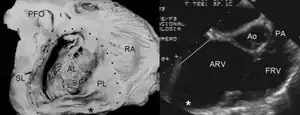

Pathological specimen and ultrasound image of a heart with Ebstein's anomaly: Abbreviations: RA: right atrium; ARV: atrialized right ventricle; FRV: functional right ventricle; AL: anterior leaflet; SL: septal leaflet; LA: left atrium; LV: left ventricle; asterisk: grade II tethering of the tricuspid septal leaflet | |